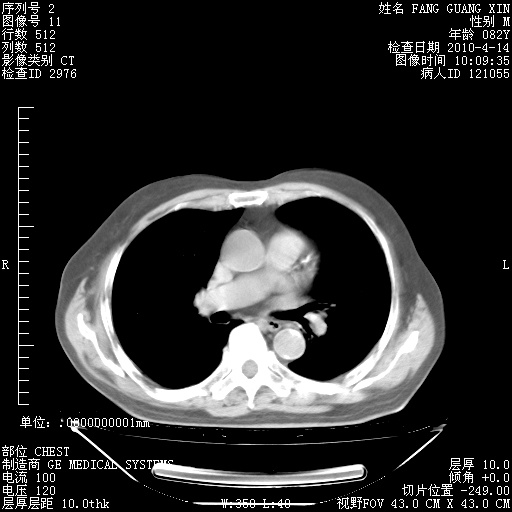

4月14日肺部CT

23.JPG

24.JPG

25.JPG

26.JPG

肺部CT平扫未见异常。